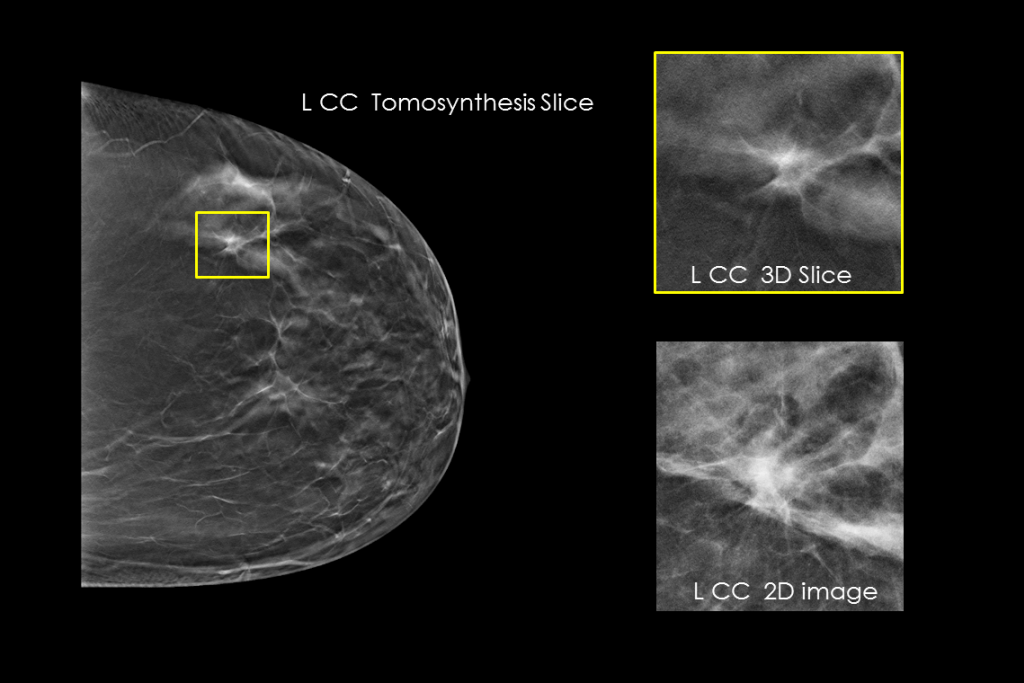

The 3Dimensions mammography system works with smart tomosynthesis technology, combining Clarity HD™ high resolution imaging, Intelligent 2D™ synthesised imaging and 3DQuorum™ SmartSlices for an efficient workflow.